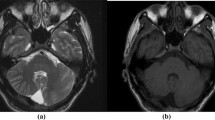

Brainstem and cerebellum

The cerebral peduncles were almost completely absent. The pontine base was extremely thin and gliotic with nearly complete lack of pontine nuclei, corticospinal and pontocerebellar tracts (Fig. 7A). Medullary pyramids were almost totally absent (Fig. 7B). The cerebellum was severely hypoplastic and dysplastic with only rudimentary hemispheres and complete aplasia of the vermis (Fig. 7A). The external granular layer was hypoplastic (Fig. 7C). The cellular arrangement of the cortex was severely disorganized (Fig. 7C, D). Large clusters of heterotopic gray matter composed exclusively of granule cells (Fig. 7E, F), and scattered single heterotopic LDNs immunoreactive for pNF and CB (Fig. 7G) were also observed in the cerebellar deep white matter. The dentate nucleus was dysplastic and identified as a collection of gray matter islands lacking the normal undulating contour (Fig. 7H). Most of the astrocytes observed in the cerebellar white matter were multinucleated (Fig. 7I), consistent with Alzheimer type I astrocytes.

A Whole mount transverse section of pons and cerebellum showing hypoplastic cerebellar hemispheres. Note severely hypoplastic pontine base. Asterisks indicate trigeminal nerves. B Inferior olivary nuclei (arrow) are hypoplastic and dysplastic, lacking hilus directed medially. Asterisk indicates hypoplastic medullary pyramids. C, D Microscopically clusters of disoriented Purkinje cells (arrow in C) and granule cells are randomly intermingled with each other without normal laminar cytoarchitecture, better demonstrated with CB immunostaining (D). The cellularity of external and internal granular layers appears less than normal. Note a Purkinje cell just beneath the external granular layer (arrow in D). E, F There is also a relatively well-organized Purkinje cell layer, although situated in the middle of the internal granular layer (asterisks in E). Note a large cluster of heterotopic gray matter composed exclusively of granule cells (arrow in E) positive for synaptophysin (F). G There are also scattered single heterotopic LDNs immunoreactive for pNF and CB observed in the deep cerebellar white matter. H The dentate nucleus is dysplastic and identified beneath the dysplastic cerebellar cortex (asterisk) as a collection of gray matter islands lacking the normal undulating ribbon-like contour (arrowheads). I Most of the astrocytes observed in the white matter are multinucleated consistent with Alzheimer type I astrocytes. A Klüver-Barrera, ×4.5; B Klüver-Barrera, ×40; C HE, ×200; D CB immunostaining, ×100; E HE, ×42; F synaptophysin immunostaining, ×66; G CB immunostaining, ×400; H synaptophysin immunostaining, ×20; I HE, ×400

Rare type of heterotopic granule cells in the cerebellum

One of the striking histological features observed in the cerebellum of this patient is the presence of heterotopias composed exclusively of granule cells without accompanying Purkinje cells (Fig. 7D, E). Heterotopias in the developing cerebellum [13, 20, 32] often coexist with other cerebellar malformations [14]. Heterotopic neurons in developing cerebellum, particularly the white matter, are often incidentally observed, but not rare, even during normal development, possibly as a temporary phenomenon during cerebellar development [32]. However, the fact that those heterotopias have been reported to be constantly associated with a Purkinje cell component [32] and that there has been no report of cerebellar white matter heterotopias composed exclusively of granule cells, suggests another yet to be defined role for Purkinje cells in the migration of external granule cells not only in normal cerebellar corticogenesis, but also in the formation of heterotopia. In fact, the Purkinje cell-derived sonic hedgehog has a mitogenic effect on granule cell precursors [8, 47, 48], and the external granule cells secrete reelin [33]. Interestingly, the granule cell heterotopias observed in the present case were morphologically well differentiated, containing synaptophysin-immunoreactive glomeruli (Fig. 7D, E) but not spindle-shaped cells described as “matrix cell heterotopia” or “residual matrix cells” [14]. Further detailed characterization is necessary to determine the precise origin of these malpositioned granular neurons.